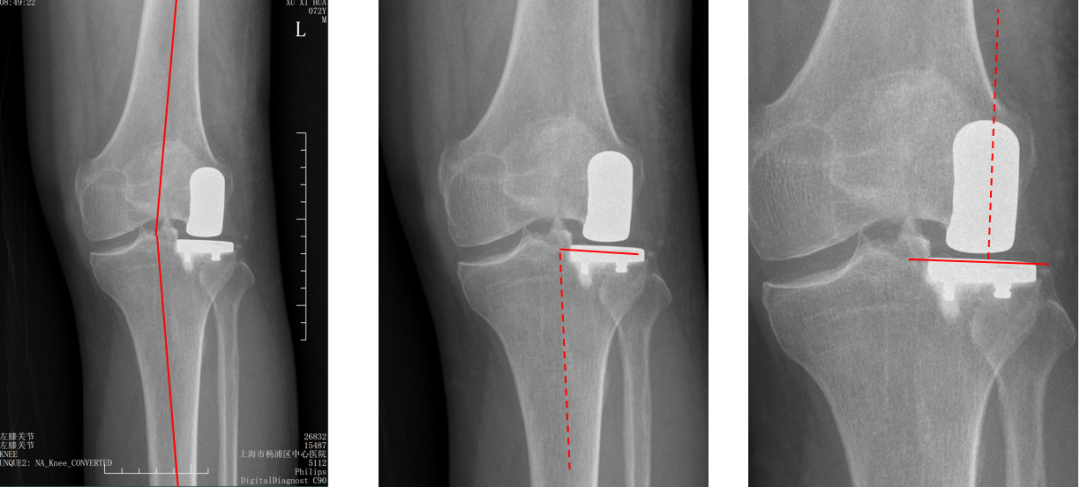

标准胫骨假体位置

AP位胫骨与股骨假体位置:胫股角10°,轻度膝外翻;水平截骨轻度外翻,外侧缘与胫骨平台外侧缘齐平; 股骨假体中轴线与胫骨假体垂直,股骨假体中心与胫骨假体中心一致。

外侧间隙过分填塞(膝内翻)

AP位胫骨与股骨假体位置:胫股角-2°,膝内翻;屈曲间隙过份填塞,关节线上移,股骨假体外翻。